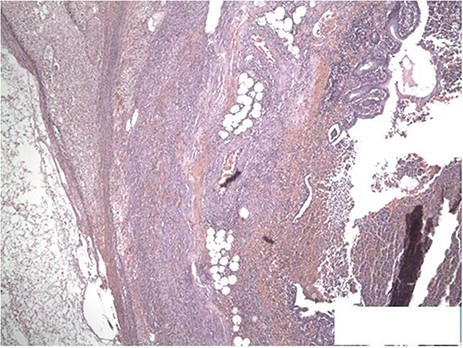

The surgical specimen received was the cecal appendix with an ovoid shape and measures of 6.5 × 4 × 3 cm. On sectioning, the appendix was 1.2 cm in diameter with a wall thickness of 0.4 cm with a sanguineous secretion inside surrounded by edematous soft tissue and vascular congestion. The section showed the cecal appendix with architectural distortion due to the acute inflammatory infiltrate with neutrophils and eosinophils that destroyed the mucinous secretory epithelium in patches and infiltrated the muscle wall and the adjacent soft tissues forming microabscesses (Figs 4 and 5). The pathology department reported acute appendicitis with microabscesses. The patient was discharged 48 hours after surgery without complications.

(A) Inflammation extends into the lamina propria. H&E ×100. Large collections of neutrophils are also seen in the lumen and in the muscle layer. (B) The inflammatory infiltrate is predominantly neutrophilic. H&E ×40.

The sections show the appendiceal wall from mucosa to serosa with transmural inflammation. Focal mucosal ulceration is seen as well as congested vessels. Crypt architecture is preserved. H&E ×40.